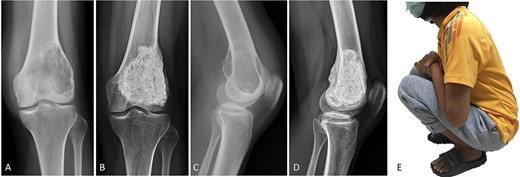

(A, C) Case no. 5: female, 23 years of age with GCTB at the distal femur without subchondral bone involvement, Campanacci grade III. (B, D) Radiograph at 81 months after extended curettage with hydrogen peroxide, phenol and cementation. (E) MSTS score 93%.